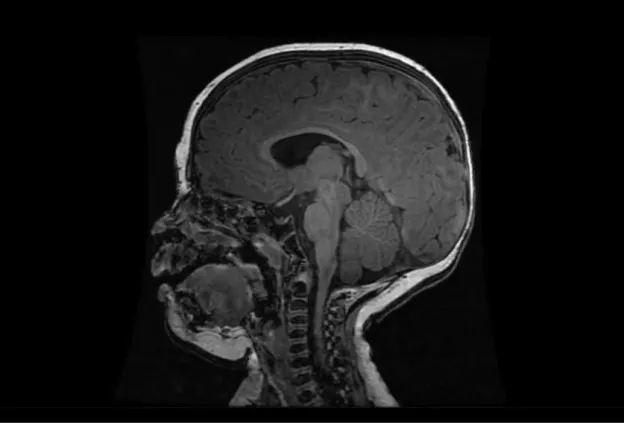

MRI Scan

MRI map of water diffusion shows bilateral posterior brain injury (dark areas) in a 5 day old baby.

The Birth Asphyxia MRI (BAMRI) project has been ongoing since 1993.  The goal was to see how sensitive MRI was in assessing brain injury of babies who had encephalopathy (abnormal neurological exam, seizures, abnormal blood gases) in the neonatal period.  We saw that brain injury occurred in certain patterns and were able to conclude that those patterns were associated with specific types of injury.  Some types of injuries resulted in damage to areas with high energy demands (brain stem, thalamus, sensorimotor pathways), while others resulted in damage to regions that got less blood flow when blood pressure went down or the heart didn’t contract forcefully.  Some babies had damage to the entire brain, presumably due to a long period with essentially no flow to the brain.  Still others, had very localized areas of injury, which we call a “stroke” or an infarct.  By looking at these patterns of injury and correlating them with outcomes when the babies came back for follow-up neurodevelopmental examinations, our team was able to predict reasonably well what outcome would be based upon the initial MRI.

As time passed, we got additional tools to use on the MRI and more powerful MRIs; these allowed us to do new and better examinations of the babies’ brains.  Proton MR spectroscopy (MRS) allowed us to look at effects of the injury on specific chemicals in the brain.  Diffusion weighted MR imaging (DWI), which looks at water motion in the brain, could show smaller areas of injury at earlier times and could be quantified to see how bad the injury was in different locations.  Even more important, MRS and DWI showed that the injury in the brain rapidly changed over the first few days; it got much worse between day 1 and day 4.  This finding was very important, because it taught us that early intervention might reduce the severity of brain injury.  This discovery led to the trial of therapeutic hypothermia (TH, also called “brain cooling”).  Recent studies have shown that brain cooling significantly reduces brain injury in some newborns, particularly those with injury to the areas with high energy demands when the injury is not very severe.  We think that the babies who do not respond well to TH have a different kind of injury, which has progressed beyond the stage where TH is effective.  Different therapies are now being formulated and will be used in upcoming trials to see if they are effective.